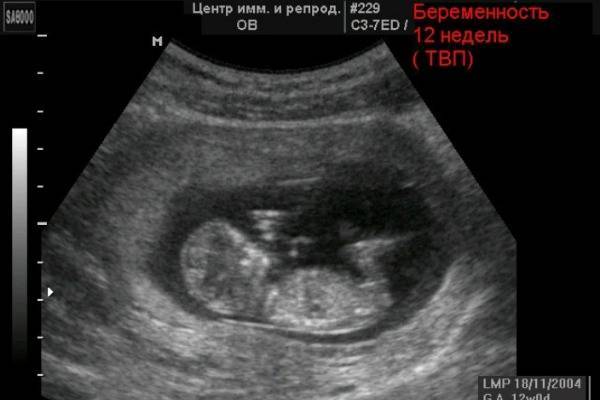

Информацию о пороках развития плода получают на 1-м УЗИ. Врач исследует размер воротниковой зоны. Значительные отклонения от нормы свидетельствует о разных заболеваниях, в том числе о синдроме Дауна.

В процессе процедуры определяется размер и вес эмбриона. В данном случае показатели варьируются в зависимости от роста родителей и некоторых других факторов. Не всегда отклонения от общепринятых значений свидетельствует об аномалиях. На 12-14 недели вес плода варьируется в пределах 14-43 г, длина 5-8, 7 см. Чем позже сделано УЗИ, тем крупнее будет плод.

В процессе процедуры определяется размер и вес эмбриона. В данном случае показатели варьируются в зависимости от роста родителей и некоторых других факторов. Не всегда отклонения от общепринятых значений свидетельствуют об аномалиях. На 12–14-й неделе вес плода варьируется в пределах 14–43 г, длина 5–8,7 см. Чем позже сделано УЗИ, тем крупнее будет плод.